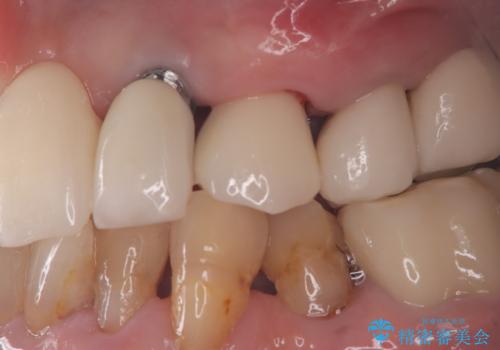

器具が破折して残ったままの前歯

- 前歯の変色が主訴で来院した患者様です。

お痛みは無く、たまに異和感があるとのことでレントゲン撮影をすると、以前根の治療をされた際の器具が破折したまま残っていました。

破折した器具を除去したのち、根管治療、ファイバーコア築造、セラミッククラウンの製作を行いました。

歯の根に器具が残っている事にビックリされていました。

セラミックは、2本行う事でより自然な仕上がりとなり、患者様もご満足していただけました。